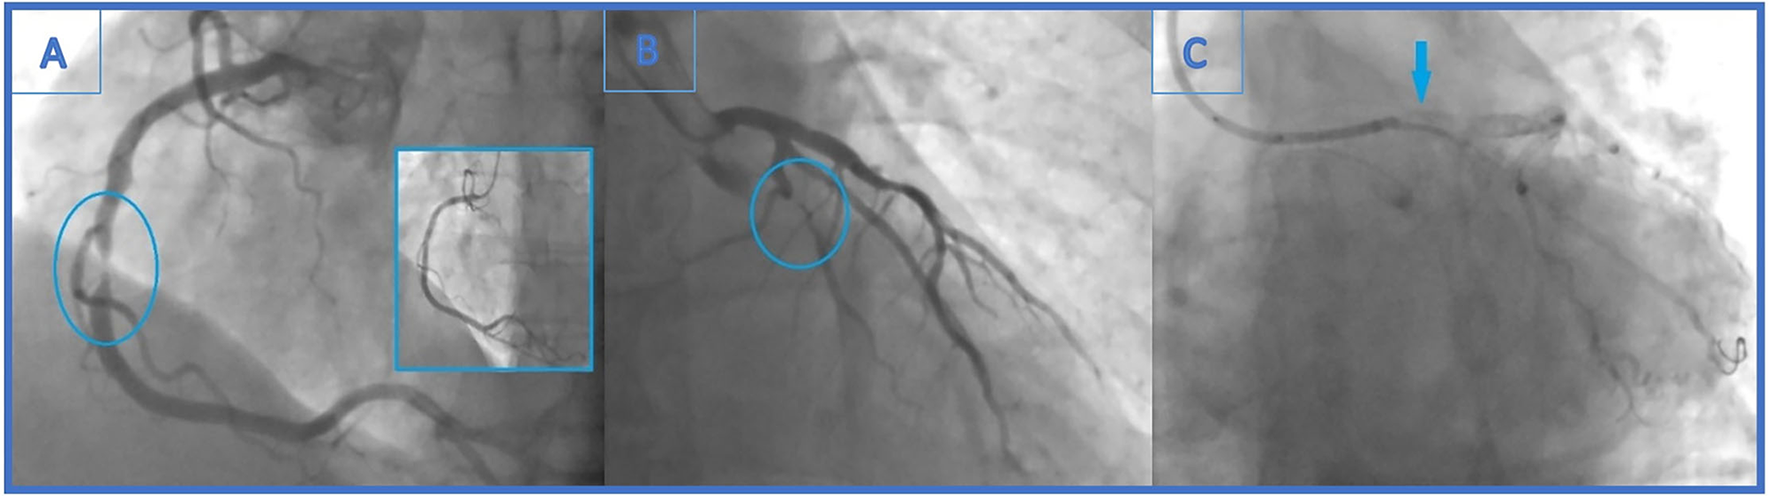

Figure 1

(A) Urgent coronary angiography with significant mid-right coronary artery stenosis (99%)-the culprit lesion and final angiographic result in the little window. (B) Distal left circumflex artery (LCx) lesion left unsolved (90% stenosis). (C) Angiogram showing stent falling from the balloon and darting into the LCx ostium. It is seen as linear radio-opaque object in the LM/LCx.

After 4 months, the patient reported effort angina (Canadian Cardiac Society—CCS class 2), and the stress-ECG test showed signs of ischaemia. Coronary angiography revealed newly formed, highly significant ostial (95%) LCx stenosis (LM 0.0.1 lesion according to Medina classification) (Figure 2A). Previously known distal LCx stenosis (90%) was also shown.

Figure 2

(A) Second coronary angiography revealed newly formed, highly significant ostial (95%) (Medina 0.0.1) LCx stenosis. Also, previously known distal LCx stenosis (90%) was shown. (B) The end of the second intervention (angiography without iodinated contrast): the lost stent in the left main coronary artery (arrow). The distal part of the lost stent (part in the LCx, 70% of its length) is crushed with the proximal LCx stent. (C) The end of the second intervention where proximal and distal LCx stenosis were solved (arrows indicating lesion sites where the stents were implanted).